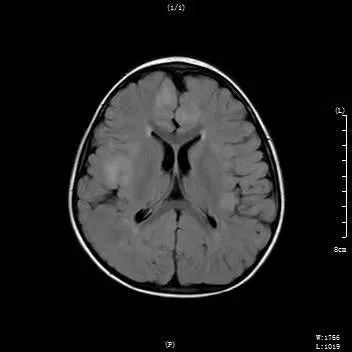

入院后,查体、完善检查,初步诊断为:1.症状性癫痫;2.结节性硬化。

【核磁检查】

因患者年龄较小,全脑多个结节,脑电图弥漫放电,病情复杂,定位困难,特邀请北京、昆明两地专家进行多学科远程会诊讨论下一步治疗方案,首都医科大学三博脑科医院癫痫中心王梦阳主任(神经内科)、王静教授(神经电生理),昆明三博脑科医院副院长功能神经外科一病区主任任杰、神经内科副主任高菁、神经电生理和磊洁等医生参加此次会诊。